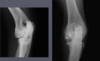

What is shown in this radiograph?

active periosteal reaction on the cranial aspect of elbow; inactive periosteal reaction on caudal aspect of humerus